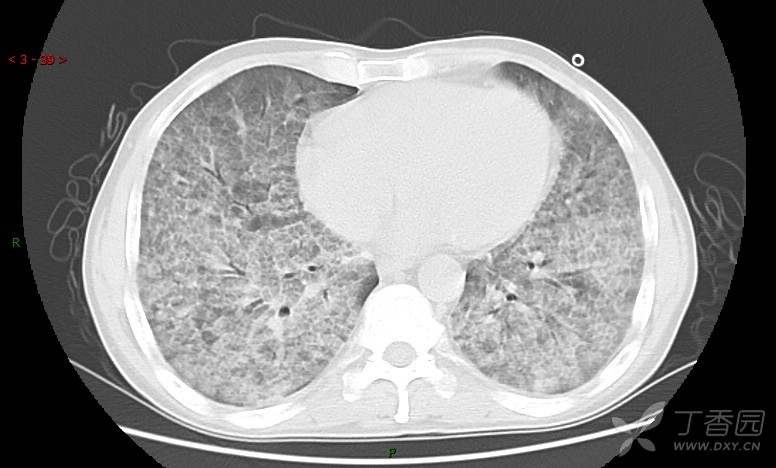

地图+铺路石征=PAP?那升高的CEA怎么说(病例3连发,附其他2例链接)

患者男,42岁,咳嗽半年余,加重伴憋喘2月余。

患者半年余前无明显诱因出现间断咳嗽,干咳为主,偶咳少量黄白痰,剧烈咳嗽或运动后可出现轻度憋喘,无高热、脓臭痰,无胸痛、咯血及晕厥,无低热乏力及盗汗,无心前区压榨感及夜间阵发性呼吸困难,初未在意,未予正规诊治。2月余前患者自觉上述症状较前加重,咳嗽、憋喘明显,黄白色粘痰略有增多,伴有发热,热前伴有畏寒、寒战,体温最高达38.9℃,先后就诊多家医院,入住重症监护室,未行气管插管,考虑“重症肺炎”,给予“美罗培南、复方磺胺甲噁唑”等药物抗感染,“卡泊芬净”抗真菌,并给予“甲泼尼龙”等药物治疗35天,经治疗后症状好转于2018-04-02出院。患者自出院后仅应用中药治疗(具体不详),并给予家庭氧疗,平素仍有间断咳嗽,咳少量黄白色粘痰,活动后憋喘明显,活动耐量差,以卧床为主。

肺内弥漫性网状结节影,PET-CT却无阳性病灶,这是?(附其他2例链接)